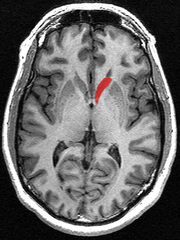

Together with the putamen, the caudate forms the dorsal striatum, which is considered a single functional structure; anatomically, it is separated by a large white matter tract, the internal capsule, so it is sometimes also referred to as two structures: the medial dorsal striatum (the caudate) and the lateral dorsal striatum (the putamen). In this vein, the two are functionally distinct not as a result of structural differences, but merely due to the topographical distribution of function.

The caudate nuclei are located near the center of the brain, sitting astride the thalamus. There is a caudate nucleus within each hemisphere of the brain. Individually, they resemble a C-shape structure with a wider "head" (caput in Latin) at the front, tapering to a "body" (corpus) and a "tail" (cauda). Sometimes a part of the caudate nucleus is referred to as the "knee" (genu).[5]

The head and body of the caudate nucleus form part of the floor of the anterior horn of the lateral ventricle. After the body travels briefly towards the back of the head, the tail curves back toward the anterior, forming the roof of the inferior horn of the lateral ventricle. This means that a coronal (on a plane parallel to the face) section that cuts through the tail will also cross the body and head of the caudate nucleus.